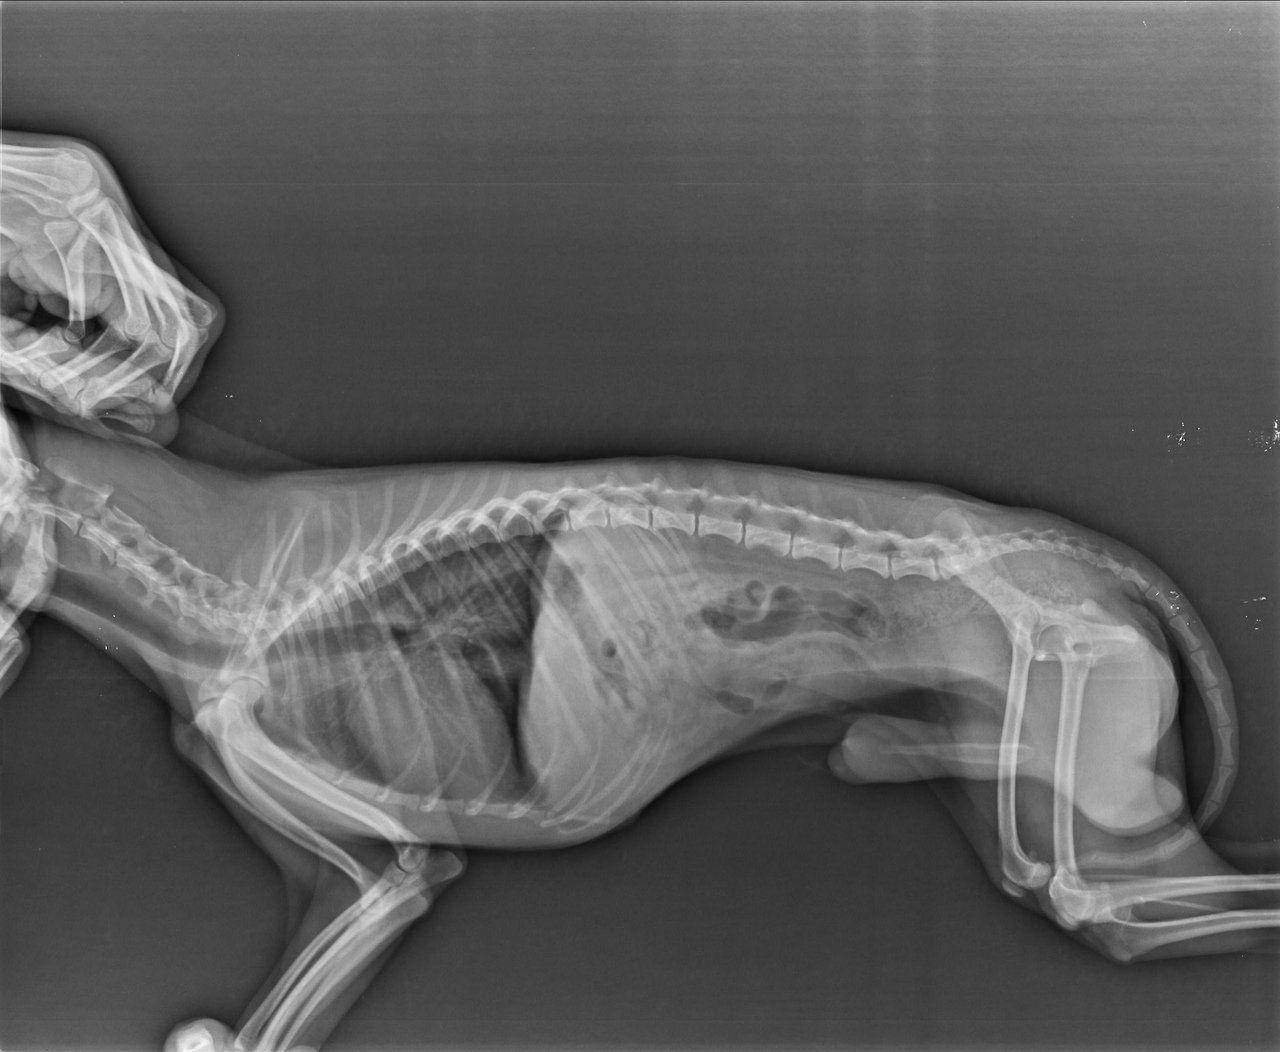

Рентгеновские снимки анатомии собак: строение и здоровье